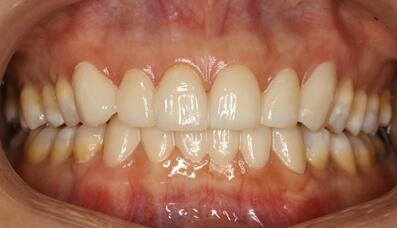

氟斑牙|瓷贴面修复——术后照片

术后开口器照

术后嘴唇照